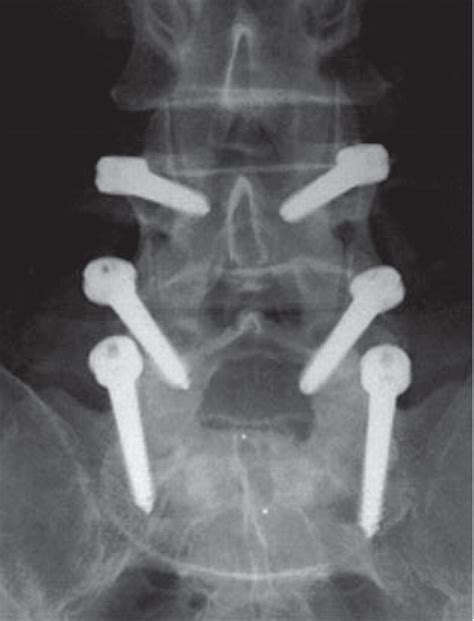

Spinal cord stimulation leads dorsal column - vrserg